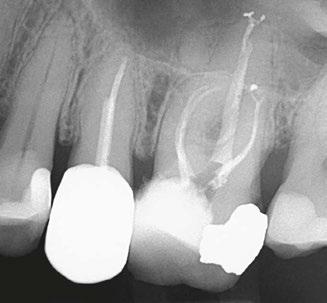

The patient was diagnosed with irreversible pulpitis in tooth number 14, which presented multiple canals with highly complex anatomies. All canals were instrumented to 25/.04 and cleaned with Odne®Clean following the recommended clinical protocol. The use of Odne®Clean enabled the identification of five canal orifices and clearing of apical deltas.

Clinical case performed by Dr. Brett Gilbert (Figures 4 and 5)

In this case, Dr. Gilbert was initially unable to locate the MB2 canal, despite thorough attempts using ultrasonic and a microscope. After performing the irrigation protocol with Odne®Clean, the MB2 became visible. Following activation, the filling material extended completely through the MB2.

Clinical case performed by Dr. Benedict Bachstein (Figures 1-3)